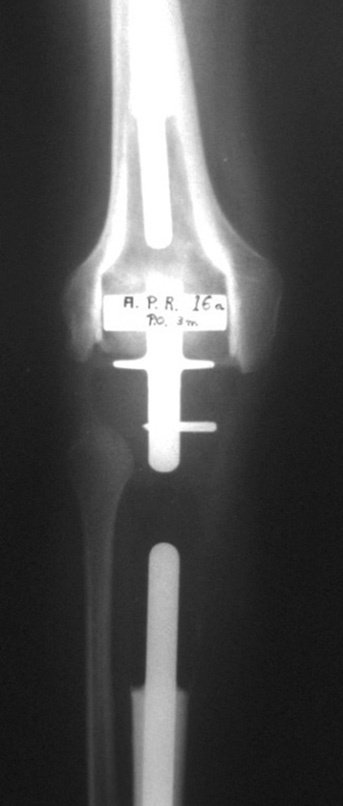

La reconstrucción se realizará con la prótesis diseñada especialmente para este paciente, fabricada en polietileno y acero inoxidable y con un componente intraepifisario en el fémur, figuras 13 a 15.

El cartílago patelofemoral debe preservarse tanto como sea posible. Con la cureta localizamos el canal femoral, figura 16. Se colocará el componente femoral entre los cóndilos femorales. Para ello es necesario realizar una osteotomía rectangular, que permita el posicionamiento adecuado del componente, figuras 17 y 18.

La fractura presentó mala consolidación, con acortamiento y desviación rotacional, resultando en protrusión del componente femoral, generando limitación funcional de la rodilla, requiriendo revisión, figuras 37 y 38. En el año 2009 se revisó la endoprótesis, figuras 39 y 40.